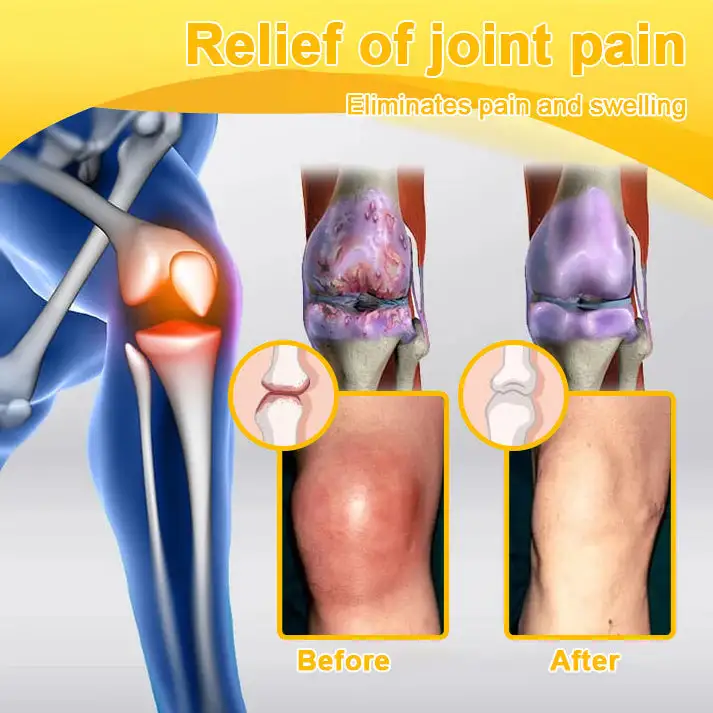

Rheumatoid Arthritis (RA) is a chronic inflammatory disease that causes inflammation and damage to the joints due to the autoimmune system attacking the synovial lining of the joints. Rheumatoid arthritis is characterized by joint pain, swelling, and stiffness, and usually occurs in small joints such as the fingers, wrists, knees, and ankles, but may affect other large joints as well.

Osteoarthritis (OA) is a common degenerative joint disease that typically worsens with age, leading to the breakdown and degeneration of joint cartilage. It is a chronic condition that most commonly affects weight-bearing joints, such as the knees, hips, spine, and hands. As cartilage wears away over time, increased friction between the bones causes joint pain, stiffness, and limited mobility.

ADNOON™ utilizes Liposome Technology to encapsulate medical-grade Botulinum Toxin and Bee Peptide, among other natural compounds, into 800nm microparticles. This technology enhances skin absorption rate to 92.3% by mimicking the structure of cell membranes, allowing rapid penetration into the joints and muscles. Botulinum Toxin quickly blocks pain signals by inhibiting neurotransmitter release, reducing joint pain. It also relaxes muscles, reduces muscle tension around the joints, and alleviates stiffness. Additionally, it has anti-inflammatory properties that reduce the release of inflammatory mediators, delaying joint degeneration.

ADNOON™ cream contains natural bee venom, which effectively improves joint flexibility. The active compound “bee venom peptide” deeply penetrates the joints, alleviating stiffness and discomfort caused by inflammation and helping to restore joint mobility. Over time, the anti-inflammatory effects of bee venom continue to promote synovial fluid production, providing better lubrication for the joints, reducing friction, and significantly improving joint flexibility within 7 days.

Botulinum Toxin blocks pain signals, while bee venom relieves pain through its bioactive compounds, providing dual pain relief. Furthermore, bee venom accelerates microcirculation and cell repair, working alongside the muscle-relaxing action of Botulinum Toxin to improve joint flexibility and repair joint tissue. This combination not only effectively alleviates joint pain but also strengthens bones, supports long-term bone health, and helps prevent osteoporosis and other bone degenerative issues.

Type II collagen is the primary component of joint cartilage and helps restore the elasticity and lubrication of the joints. It plays a crucial role in slowing down joint degeneration and repairing damaged cartilage. Taking collagen can strengthen the structure of the joints and prevent pain and discomfort caused by joint wear and degeneration. Combined with ingredients such as bee venom and magnesium oil, it can enhance the overall effectiveness of treatment and promote joint health.

“As an orthopedic doctor, I highly recommend ADNOON™ Botulinum Toxin & Bee Venom Pain Relief and Bone Healing Cream for patients suffering from osteoarthritis, rheumatoid arthritis, and other inflammatory joint and bone conditions. This cream contains botulinum toxin, bee venom extract, glucosamine, chondroitin, and other highly effective active ingredients that help reduce inflammation, nourish the joints, and enhance mobility. It also aids in rebuilding and restoring cartilage and bone tissue, relieving pain and stiffness, while eliminating harmful crystals that may accumulate in the joints, ultimately improving overall joint function.“